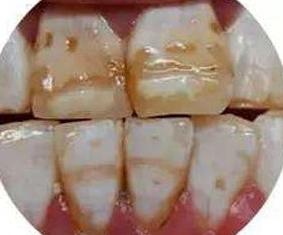

*个别牙齿上出现的白斑(如门牙):牙釉质发育不全(轻度),常出现在切牙中部和切端。

牙齿局部脱矿(下图)

*氟斑牙:氟主要损害牙釉质发育期牙胚的造釉细胞,因此,过多的氟只有在牙发育矿化期进入机体,才能发生氟牙症(六七岁之前,避免儿童在高氟地区)

临床上常按其轻、中、重度而分为白垩型(轻度)、变色型(中度)和缺损型(重度)三种类型。